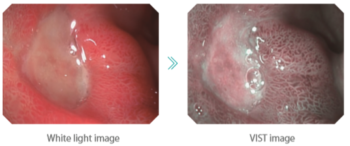

Зургийг энгийн цагаан гэрэл эсвэл VIST технологи ашиглан авах боломжтой

VIST технологи нь тод, ялгаралттай контраст үүсгэж, судас болон салст бүрхүүлийг илүү тод харуулна

VIST нь эмгэг өөрчлөлтийг илрүүлэх, ангилахад тусална

VIST – Дүрс сайжруулалтын технологи

VIST нь оптик болон дижитал дүрс боловсруулалтыг хослуулсан хромоэндоскопийн технологи юм. Зөвхөн нэг товч дарахад л гэдэсний замын салст болон судасны бүтцийг илүү тодруулан харуулах цэвэр, өндөр ялгаралттай дүрсийг үзүүлдэг. Ингэснээр эмгэг өөрчлөлтүүдийг (lesions) илрүүлэх, онцлогийг тодорхойлох үйл явц хялбар болдог.